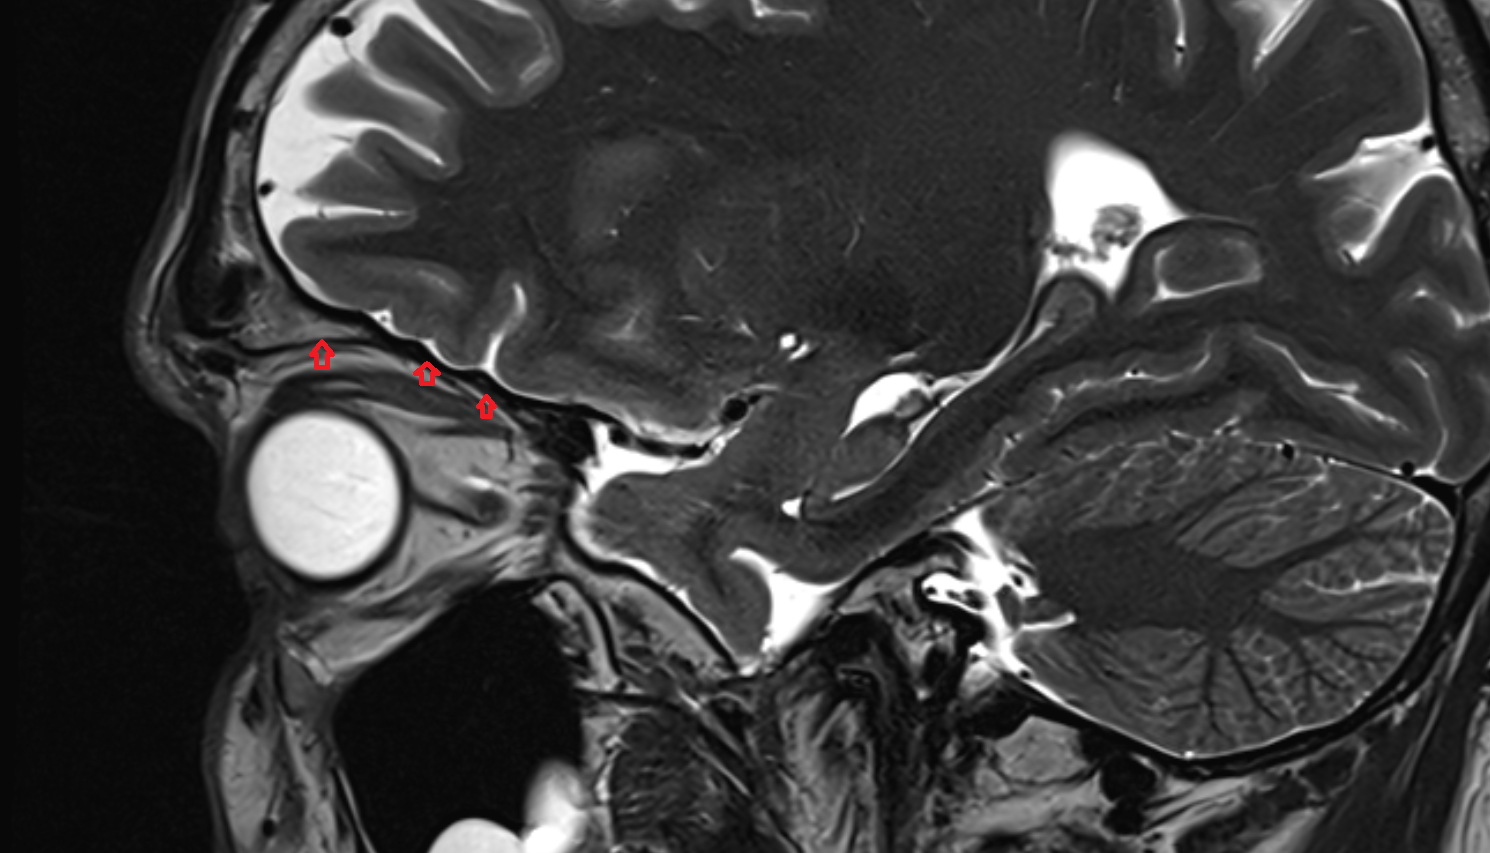

- Temporomandibular joint